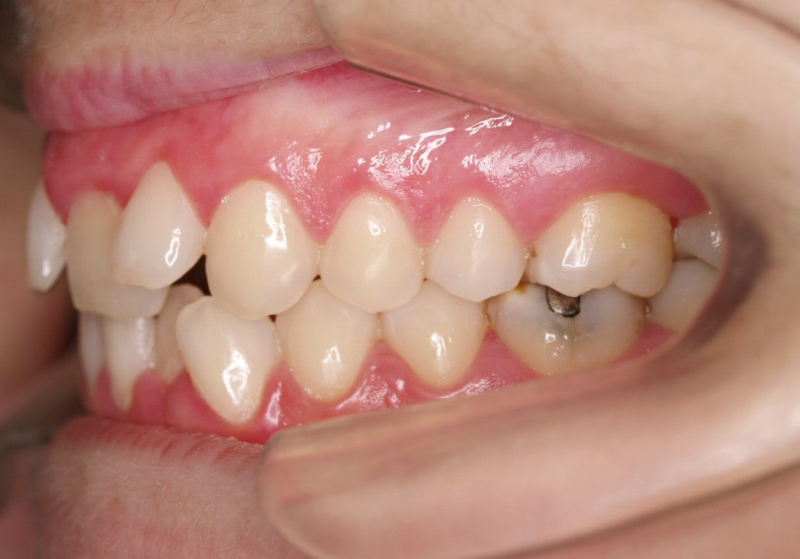

Premolar mandibular incluido + fenestración

45 incluido

Radiografía de final de tratamiento